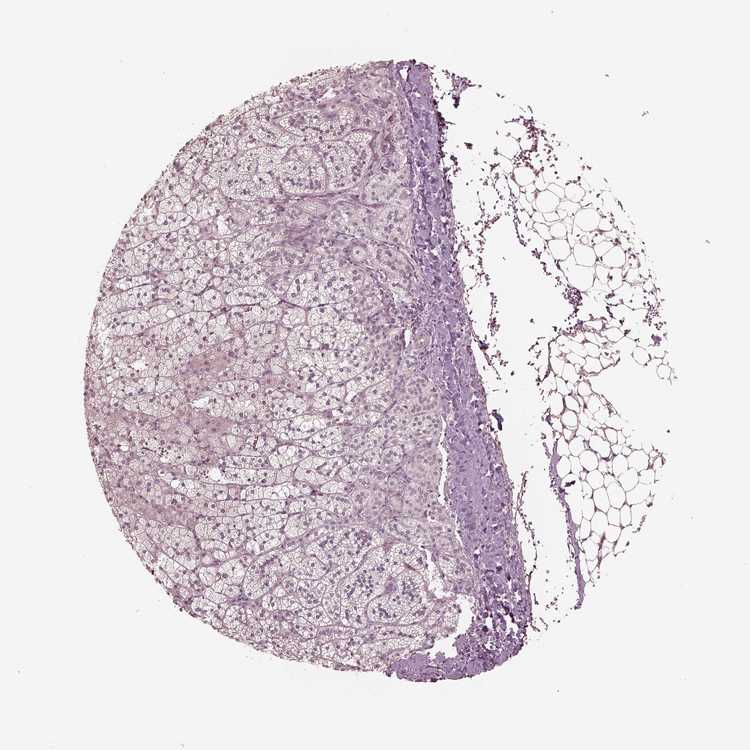

ADRENAL GLAND - Antibody stainingi

Antibody staining in the annotated cell types in the current human tissue is reported as not detected, low, medium, or high, based on conventional immunohistochemistry profiling in selected tissues. This score is based on the combination of the staining intensity and fraction of stained cells.

Each image is clickable and will lead to virtual microscopy that enables deeper exploration of all samples and also displays staining intensity scores, fraction scores and subcellular localization as well as patient and tissue information for each sample.

Antibody HPA064829

Glandular cells Not detected